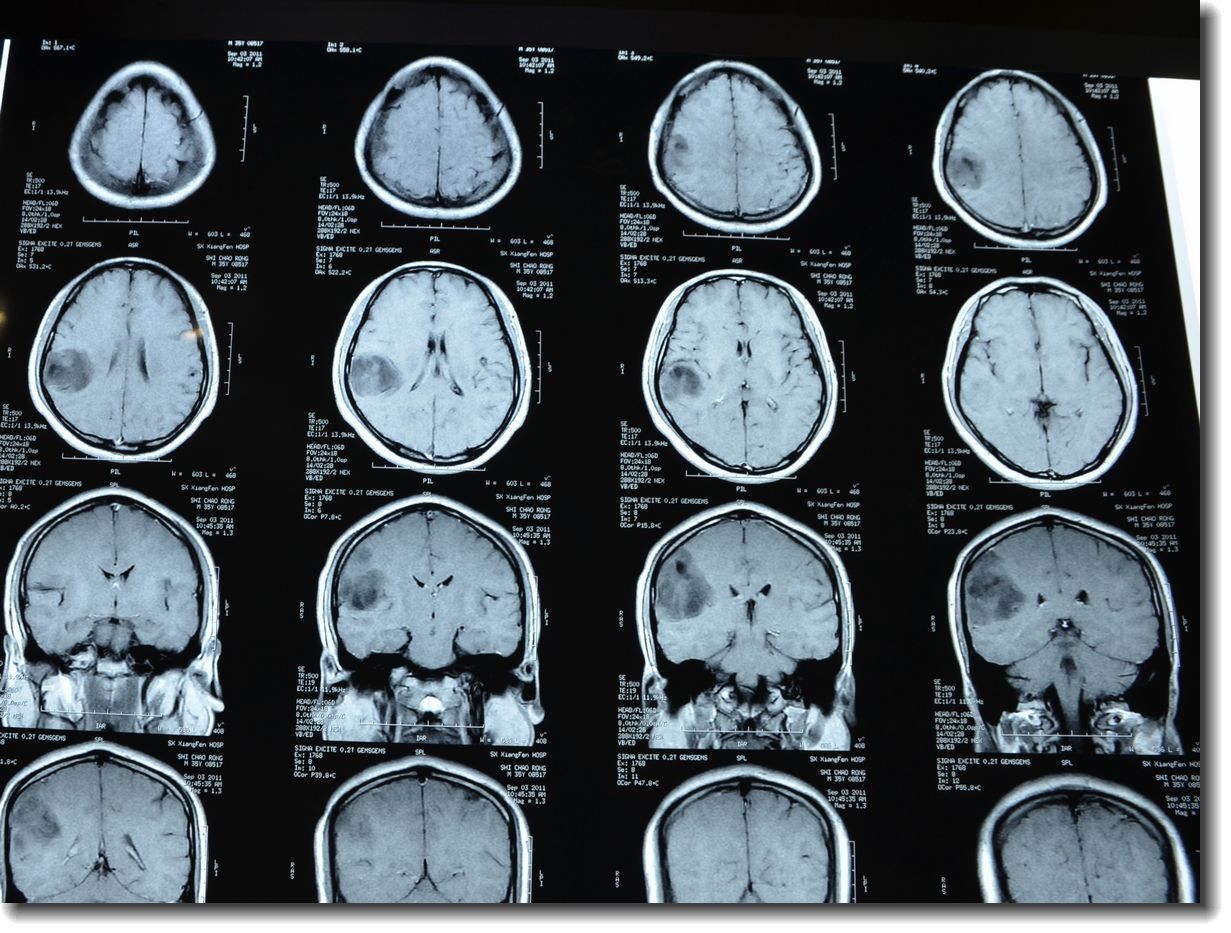

上皮样胶质母细胞瘤一例(2018华东胶质瘤mdt病例二)--浙二神外周刊(第

阔然开朗高文昌副教授团队胶质母细胞瘤1例诊疗分享

贺晓生教授胶质瘤手术治疗实例展播